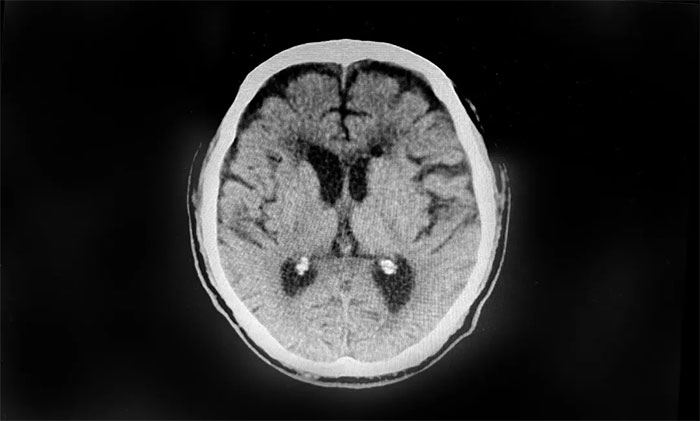

▲ 術(shù)后復(fù)查,血腫得到明顯改善

待病情穩(wěn)定并評估后,近期,于耀宇主任又為患者開展了雙側(cè)“硬腦膜下鉆孔引流術(shù)”,促使硬膜下積存的大量血腫快速排出,解除腦組織壓迫,緩解頭暈、肢體乏力等癥狀。術(shù)后,患者健康狀況平穩(wěn),病情正逐漸好轉(zhuǎn)。